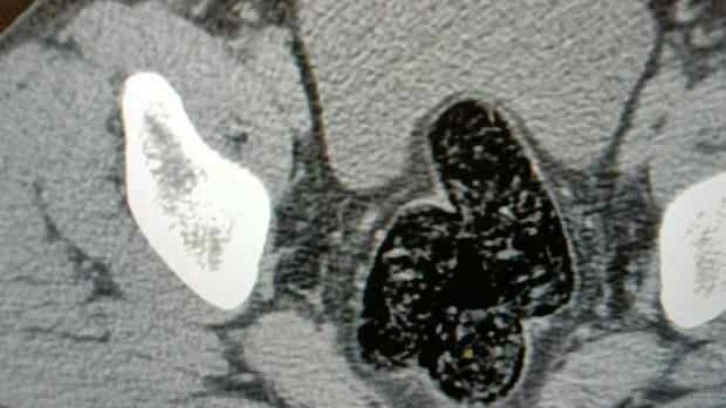

Şahsın devam eden işlemlerinde gözlerindeki kızarıklık, yemek ihtiyacı istememesi, aşırı tedirgin davranışlar sergilemesi üzerine yapılan iç beden muayenesi neticesinde röntgen vasıtasıyla makat ve bağırsak kısmında uyuşturucu kapsülleri olduğu tespit edildi. Doğal yöntemlerle şahıstan 12 adet kapsül toplam daralı ağırlığı 345.19 gram gelen metamfetamin ele geçirildi. Şahsın üzerinden ve iç bedeninden toplamda 355.36 gram uyuşturucu madde ele geçirildi.